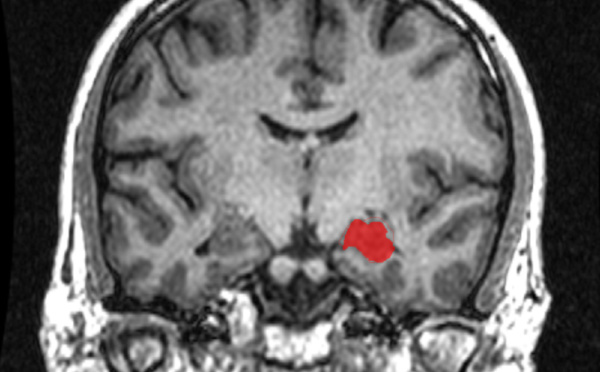

El hipocampo de hombres y mujeres es igual de grande - 02/11/2015

Una investigación realizada en EE.UU. mediante resonancia magnética desmiente la creencia generalizada de que el hipocampo, una parte crucial del cerebro que consolida nuevos recuerdos y ayuda a conectar las emociones con los sentidos, es mayor en las mujeres que en los hombres.

Aprender a navegar espacialmente produce cambios en el cerebro - 28/10/2015

Científicos de Estados Unidos han demostrado que el aprendizaje para navegar espacialmente produce cambios en el cerebro, en especial en el hipocampo. Ya se sabía, por ejemplo, que los taxistas de Londres, tenían un alargamiento en esta región, pero no se sabía cuál era la causa y cuál la consecuencia.